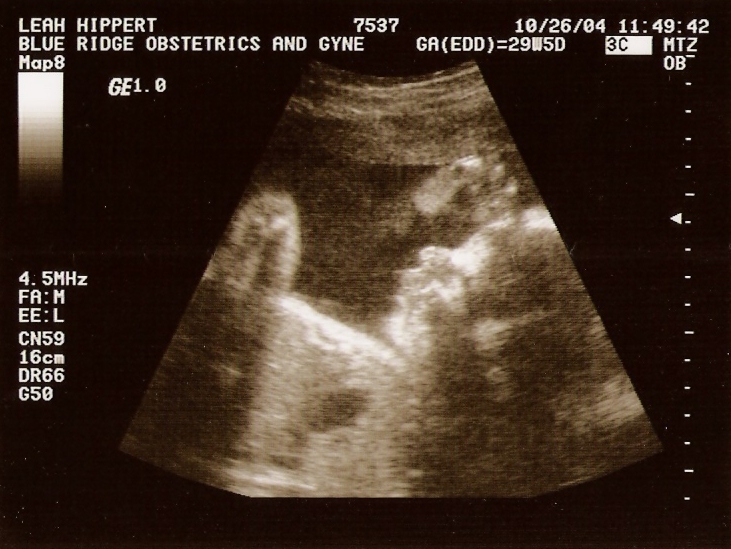

Ultrasound

Taken On October26th 2004   Taken On October26th 2004   Taken On October26th 2004